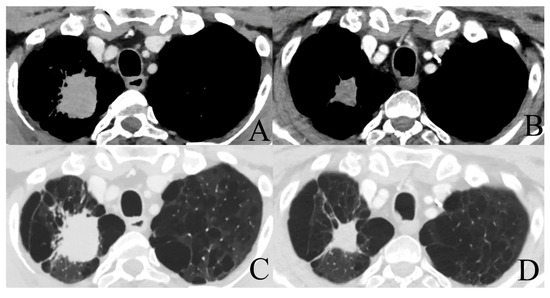

The CheckMate 816 trial investigates the same population of patients with stage IB-IIIA NSCLC. Primary endpoint are pCR and event-free survival. Secondary endpoints are MPR and OS. Three arms are used; nivolumab plus ipilimumab, nivolumab plus platinum-doublet chemotherapy, and platinum-doublet chemotherapy only, all of them in a neoadjuvant setting. A total of 624 patients will be enrolled. Results are expected in May 2023 [37]. Figure 1 shows an example of a patient with a stage IIIA NSCLC treated with four cycles of neoadjuvant cisplatinum/pemetrexed and nivolumab prior to surgical resection. Final pathology revealed a pCR and the patient had an excellent recovery.

Figure 1. Chest CT-scan with intravenous (IV) contrast showing a stage IIIA NSCLC of 42 mm × 35 mm in the right upper lobe pre-induction therapy with a volume reduction after 4 cycles of neoadjuvant cisplatinum/pemetrexed + nivolumab (27 mm × 22 mm) ((A,B): mediastinal window; (C,D): lung window).